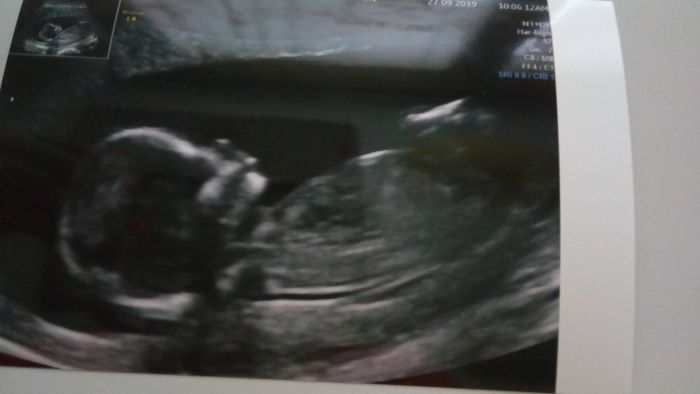

Jinak dnešní první screening dopadl výborně, krev i ultrazvuk v pořádku, tak jsme si oddychli. Jo a vypadá to na chlapečka - doktor " něco" viděl trčet mezi nožkama

Tak přítel je šťastný jak blecha. Ale lépe to půjde vidět až při druhém screeningu. Za týden jsou u nás hody, takže se sejde celá rodina, tak jim to oznámíme. Jsem zvědavá jak budou reagovat dcery

[1129717]Evi krasna fotecka a super vysledky.

[1129717] Přidávám se, krásná fotečka :)....když jsem ukazovala utz obrázky malého tetám (mamčina sestra a sestřenice) tak byly obě úplně udivené, že už takto brzy je ten červíček takový človíček :)